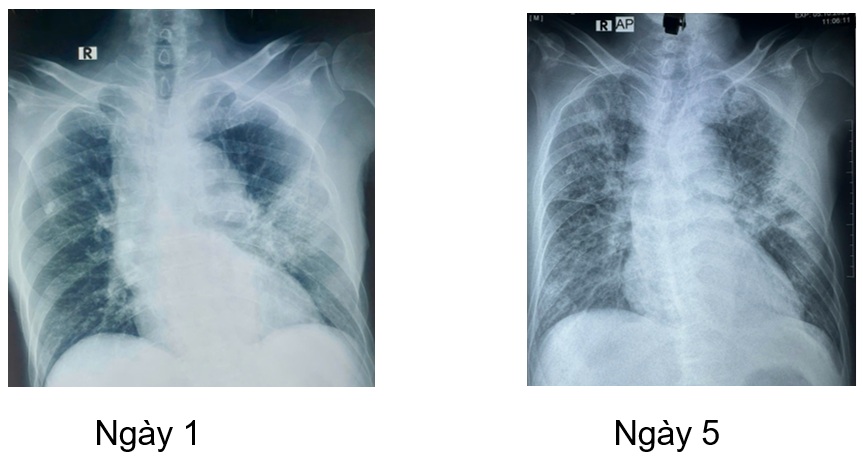

Một trường hợp lâm sàng tại khoa Nội tổng hợp, bệnh nhân nam L.V.R 80 tuổi, vào viện vì sốt, tiêu lỏng kèm khó thở, nặng ngực. Tiền sử tăng huyết áp, chưa ghi nhân bệnh lý hô hấp, bệnh mạn tính khác trước đó. Bệnh nhân nhập viện với tình trạng nhiễm trùng nhiễm độc, tổn thương thận cấp. Trong quá trình nằm viện bệnh nhân khó thở tăng dần suy hô hấp, sốt cao dao động 39 – 400C, đáp ứng kém với phác đồ kháng sinh ban đầu (piperacillin/tazobactam + levofloxacin). Bệnh nhân được nội soi phế quản, sau 5 ngày nhập viện kết quả cấy dịch rửa phế quản Candida albican, bệnh nhân được chỉ định phối hợp sử dụng kháng nấm anidulafungin. Sau 4 ngày sử dụng kháng nấm, lâm sàng bệnh nhân cải thiện hết sốt, ngưng được oxy, thở đều êm, chức năng thận hồi phục.

Bệnh nhân được tiếp tục duy trì phác đồ kháng nấm anidulafugin và fluconazole (hạ bậc kháng nấm), trong quá trình điều trị bệnh nhân được khám chuyên khoa mắt, theo dõi men gan, chức năng thận, bilan nhiễm trùng cũng như hình ảnh học (CTscan ngực, xquang ngực thẳng). Dưới đây một vài hình ảnh học trong quá trình điều trị nội, ngoại trú.